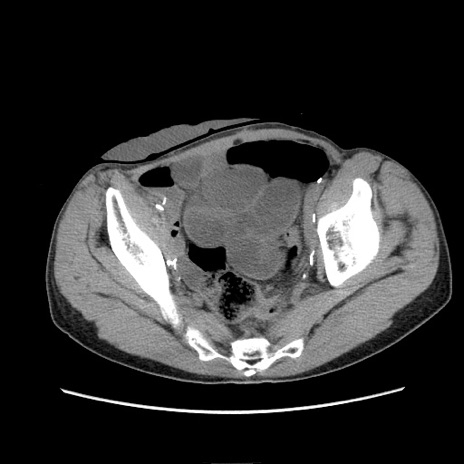

症例11(横断像)

【症例】 60歳代男性

【主訴】 下腹部痛

【現病歴】 本日夜中より下腹部痛の症状認め、受診。

【既往歴】 膀胱癌(膀胱全摘+尿管皮膚瘻術) 、胃癌術後

【身体所見】 BT 35.3℃、PR 58/min、BP 136/98mHg、腹部平坦、軟、腸蠕動音±、ストマ留置あり、左上腹部~正中部に圧痛あり、反跳痛なし。

【データ】WBC 5100、CRP0.01